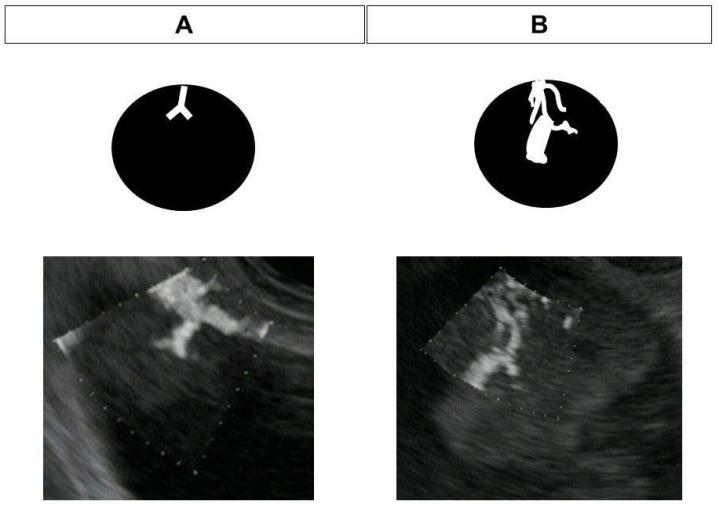

Detective flow imaging endoscopic ultrasonography (DFI-EUS) is an innovative imaging modality that was developed to detect fine vessels and low-velocity blood flow without contrast agents. We evaluate its utility for the differential diagnosis of gallbladder lesions and intraductal papillary mucinous neoplasms (IPMNs). We enrolled patients who underwent DFI-EUS, e-FLOW EUS, and contrast-enhanced EUS for gallbladder lesions or IPMNs. The detection of vessels using DFI-EUS and e-FLOW EUS was compared with that via contrast-enhanced EUS and pathological findings. The vessel pattern was also categorized as regular or irregular. Of the 33 lesions included, there were final diagnoses of 13 IPMNs and 20 gallbladder lesions. DFI-EUS was significantly superior to e-FLOW EUS for discriminating between mural nodules and mucous clots and between solid gallbladder lesions and sludge using the presence or absence of vessel detection in lesions ( = 0.005). An irregular vessel pattern with DFI-EUS was a significant predictor of malignant gallbladder lesions ( = 0.002). DFI-EUS is more sensitive than e-FLOW-EUS for vessel detection and the differential diagnosis of gallbladder lesions and IPMNs. Vessel evaluation using DFI-EUS may be a useful and simple method for differentiating between mural nodules and mucous clots in IPMN, between solid gallbladder lesions and sludge, and between malignant and benign gallbladder lesions.

侦探流成像内镜超声检查(DFI-EUS)是一种创新的成像方式,其开发目的是在不使用造影剂的情况下检测细小血管和低速血流。我们评估其在胆囊病变和导管内乳头状黏液性肿瘤(IPMN)鉴别诊断中的效用。我们纳入了接受DFI-EUS、e-FLOW EUS和对比增强EUS检查的胆囊病变或IPMN患者。将DFI-EUS和e-FLOW EUS检测血管的情况与对比增强EUS及病理结果进行比较。血管形态也分为规则或不规则。在纳入的33个病变中,最终诊断为13个IPMN和20个胆囊病变。在通过病变中血管检测的有无来鉴别壁结节与黏液凝块以及实性胆囊病变与胆泥方面,DFI-EUS显著优于e-FLOW EUS(P = 0.005)。DFI-EUS显示的不规则血管形态是恶性胆囊病变的显著预测指标(P = 0.002)。DFI-EUS在血管检测以及胆囊病变和IPMN的鉴别诊断方面比e-FLOW-EUS更敏感。使用DFI-EUS进行血管评估可能是一种有用且简单的方法,可用于鉴别IPMN中的壁结节与黏液凝块、实性胆囊病变与胆泥以及恶性与良性胆囊病变。